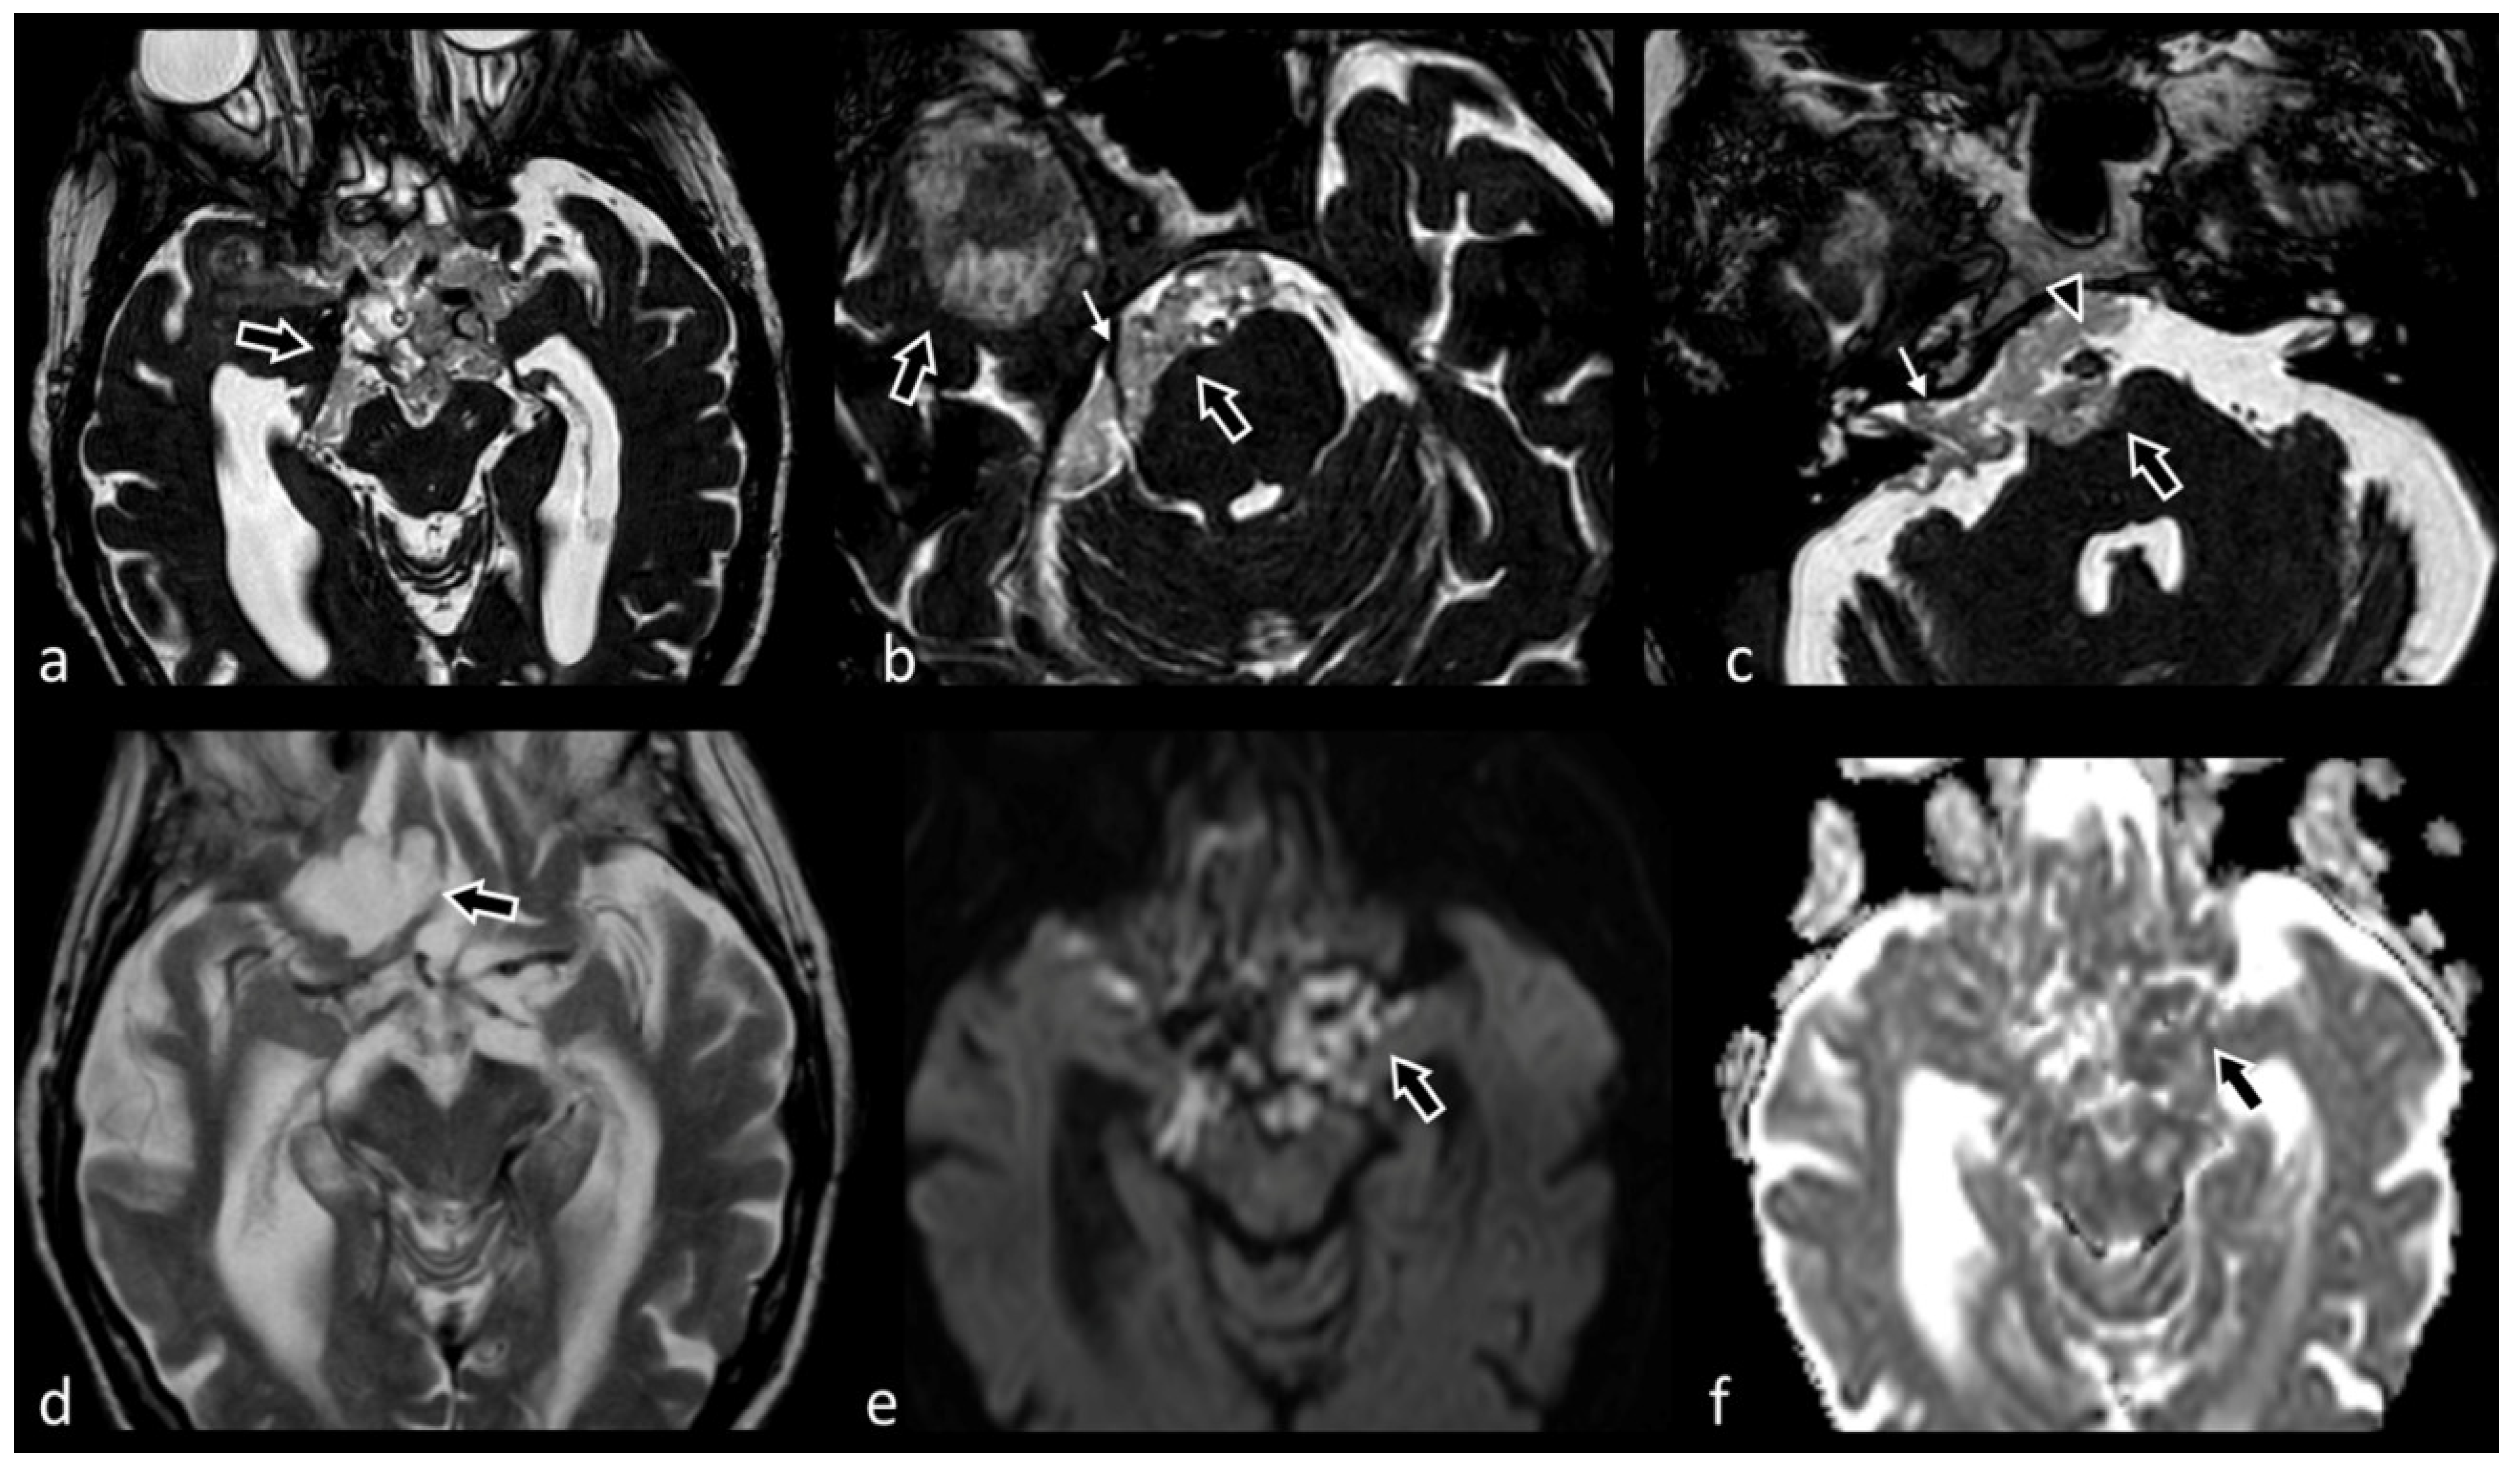

3.1.4. Trigeminal Nerve (V)

3.1.5. Facial and Vestibulocochlear Nerves (VII–VIII Complex)

3.1.6. The Lower Cranial Nerves: Glossopharyngeal, Vagus, Accessory and Hypoglossal Nerves (IX–X–XI–XII)